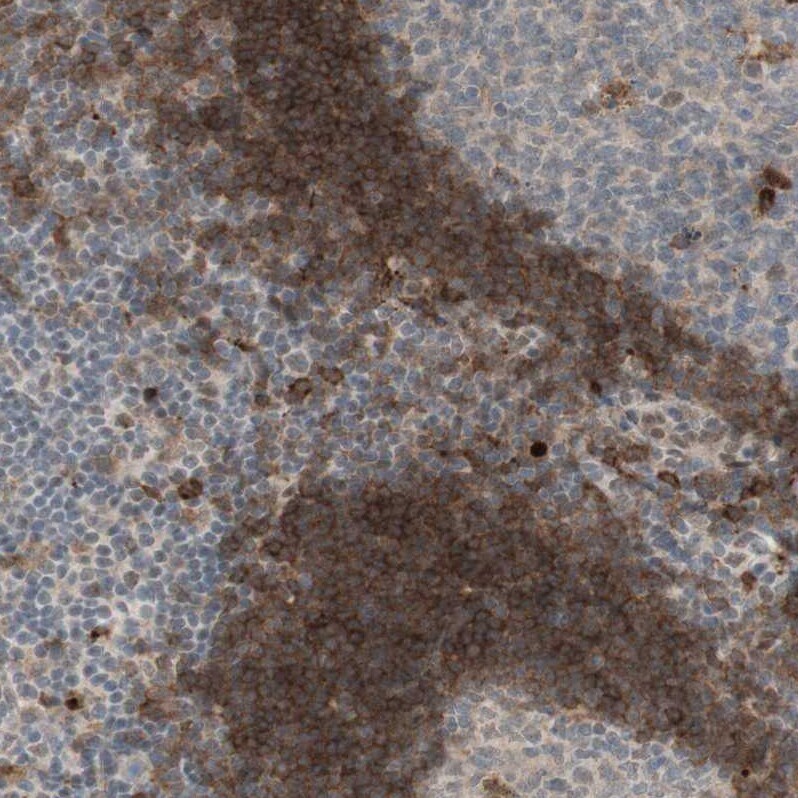

- Immunohistochemical analysis of GAPT in human tonsil using GAPT Polyclonal Antibody (Product # PA5-52785) shows strong membranous positivity in non-germinal center cells.